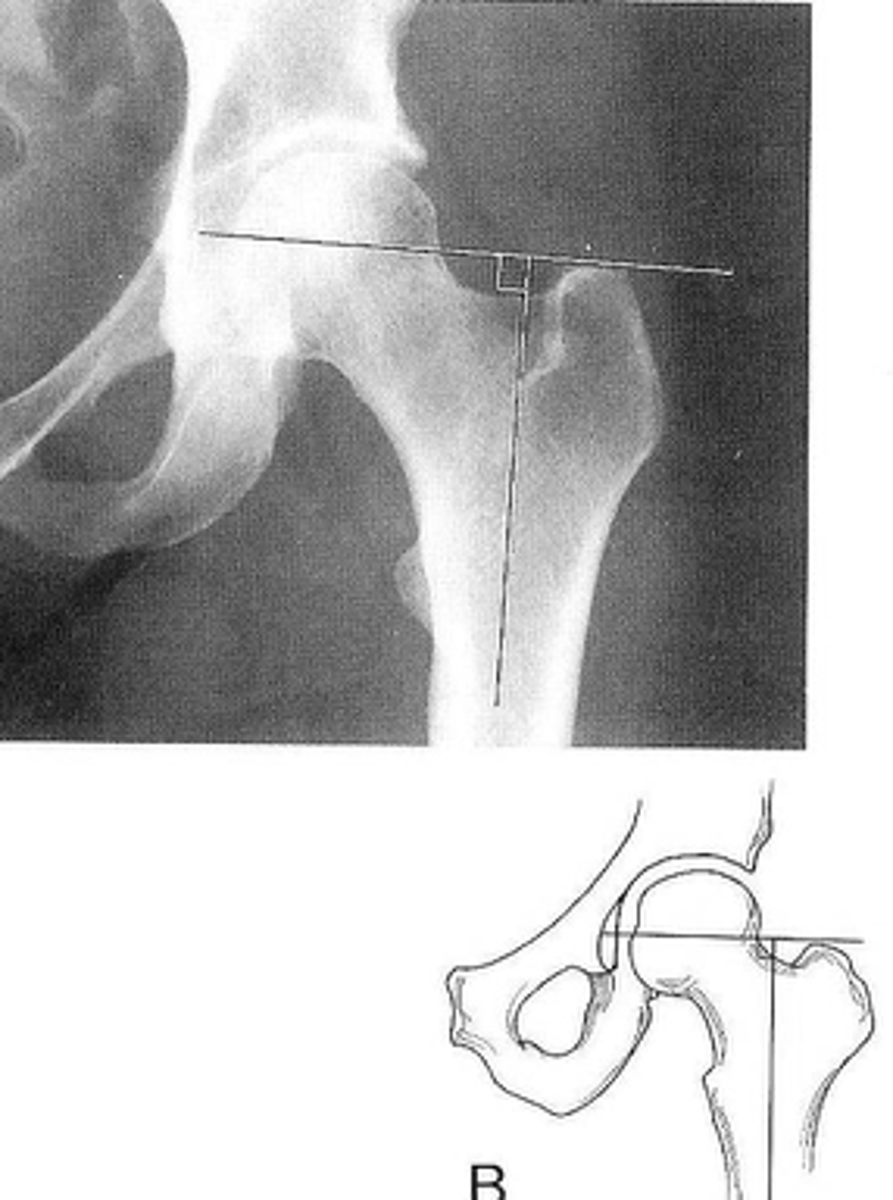

9

New cards

Right: gluteus medius

Left: gluteal fat stripe

ID 5

<p>ID 5</p>

10